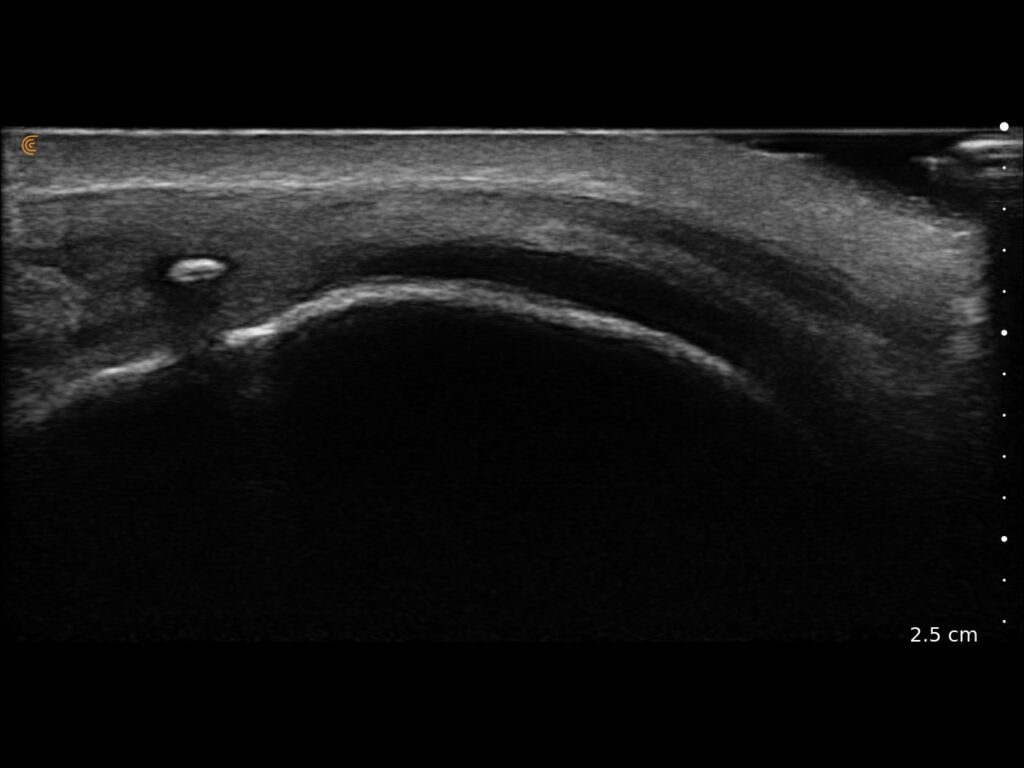

Precise Injections. Better Results.

Visualize targets in real time for precise nerve blocks and corticosteroid injections—reducing injectate volumes and boosting safety, confidence, and patient outcomes.